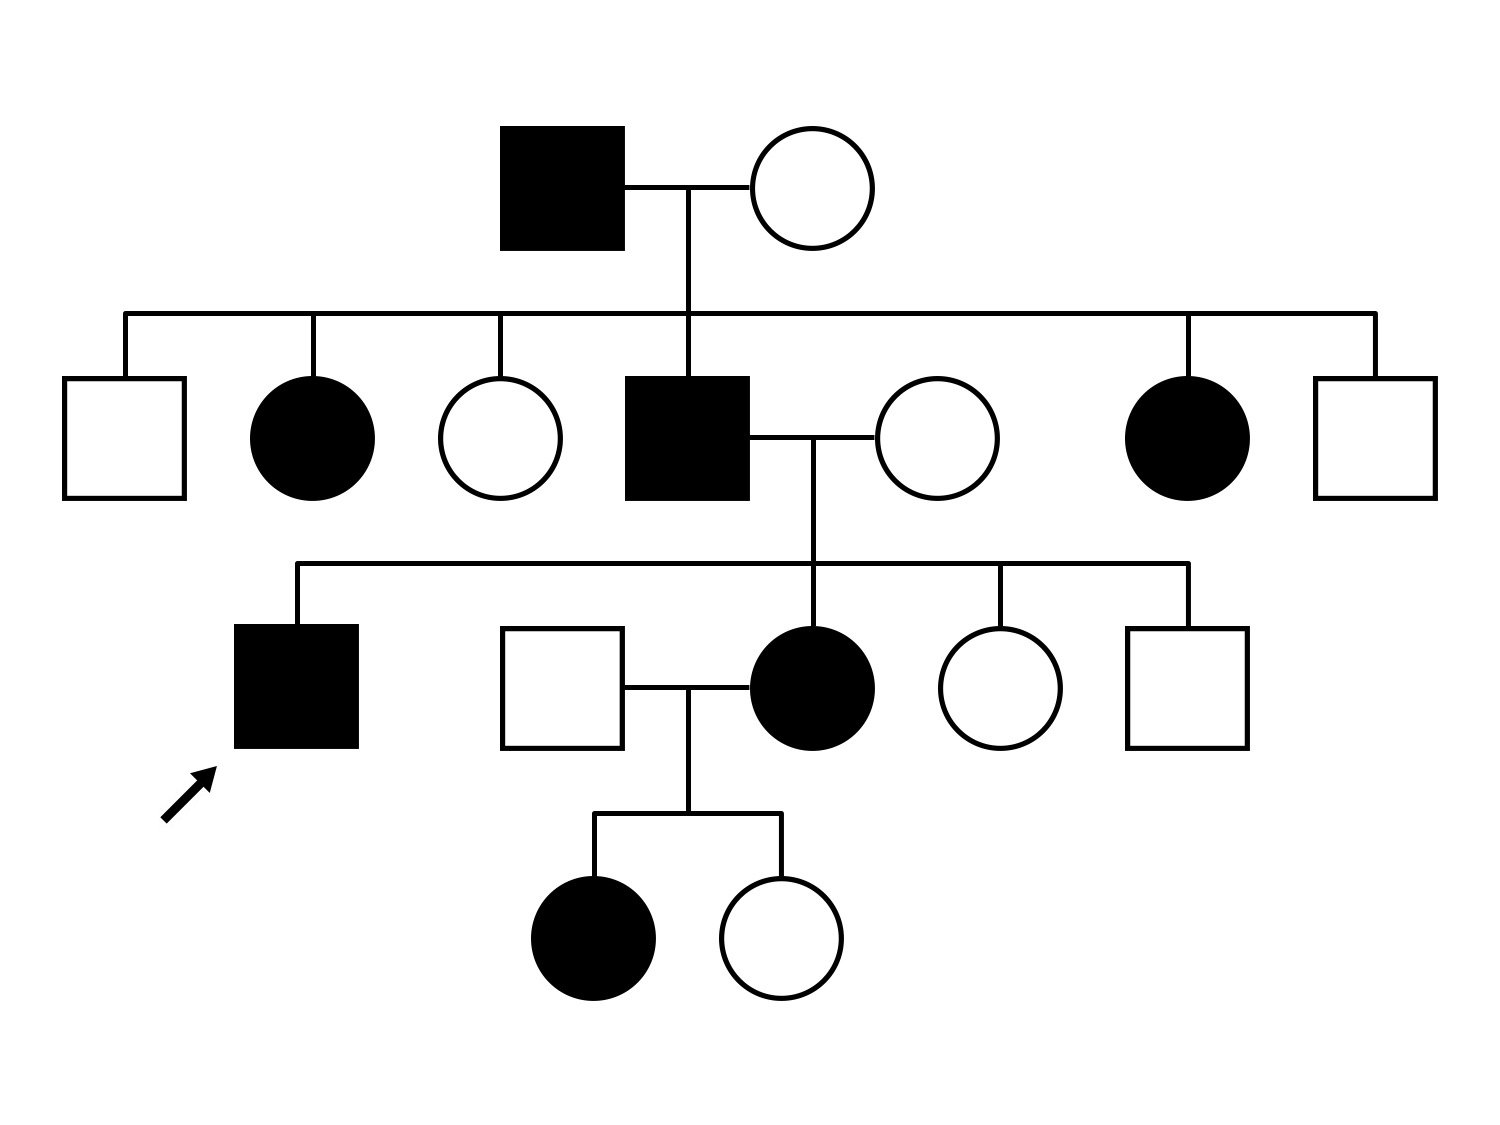

This 81 year old man began using a flashlight to read menus in his 40's. At age 75 his ophthalmologist noticed abnormal fundus findings and referred him to a retina specialist.

| Late Onset Retinal Dystrophy | C1QTNF5 | Ser163Arg AGC>AGA | AD |

Inheritance:

AD